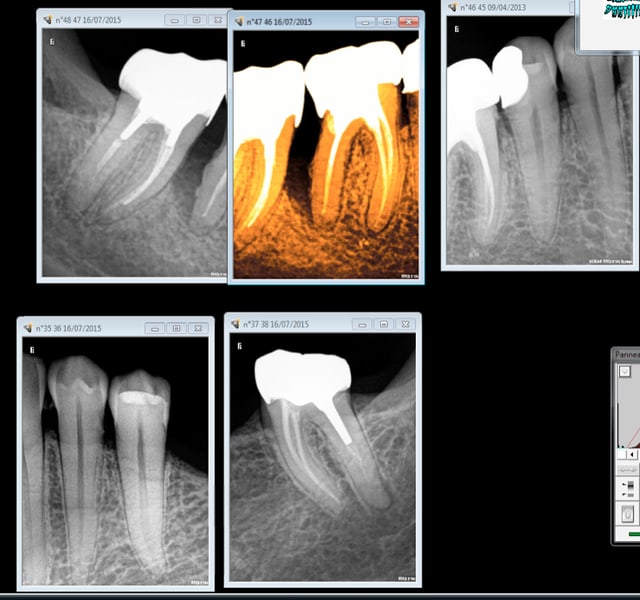

Je comprends pas ce que ça veut dire "ceux qui sont passé au NPNC". Ils font quoi là par exemple? (désolé j'arrive par à l'exporter avec traitement et rotation)

Npnc - Eugenol

Là sans doute un implant.